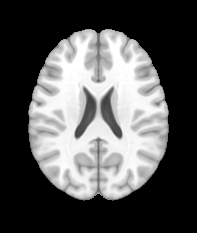

Fig. 1 shows example images from each dataset to illustrate image variability. IBSR and LPBA40 contain images from normal subjects and include large portions of the neck; BRATS has very low out-of-plane resolution; and the TBI dataset contains large pathologies and abnormal skulls.

Refer to caption

Figure 1: Illustration of image appearance variability on a selection of images from each (evaluation) database. From top to bottom: IBSR, LPBA40, BRATS and TBI.